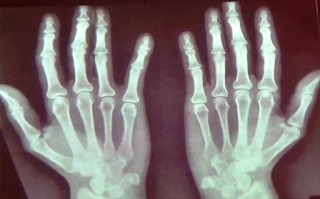

En la imagen de arriba observamos la diferentes osteologías entre los

huesos de la mano en el niño, el adulto y el anciano de izquierda a derecha

respectivamente. La presentación radiográfica que presentaran las estructuras

anatómicas dependen de su estadio de evolución y desarrollo tanto en el estado

normal como patológico.

Lo primero que podemos notar en este tipo de comparaciones es la densidad

radiográfica, que depende de la densidad ósea de la estructura anatómica. Por

ejemplo en la figura que presentamos más arriba observamos que la imagen del

extremo derecho los huesos de la mano presentan una marcada osteoporosis y

diversas subluxaciones en las articulaciones metacarpo falángicas producto de

la artritis reumatoidea. En la imagen de la izquierda no se observan los huesos

del carpo, por ello sabemos que se trata de un niño probablemente de menos de 6

meses en la que las matrices óseas de calcificación están en desarrollo. En

lugar de los huesos del carpo que normalmente veríamos en la radiografía de un

adulto observaremos un espacio en gris producto del paso de la radiación a

través del cartílago (permeable a la radiación).